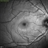

- red-free

Optical coherence tomography system

Heidelberg Spectralis - Description

- Green reflectance of a 30 yo female with PAMM OD.